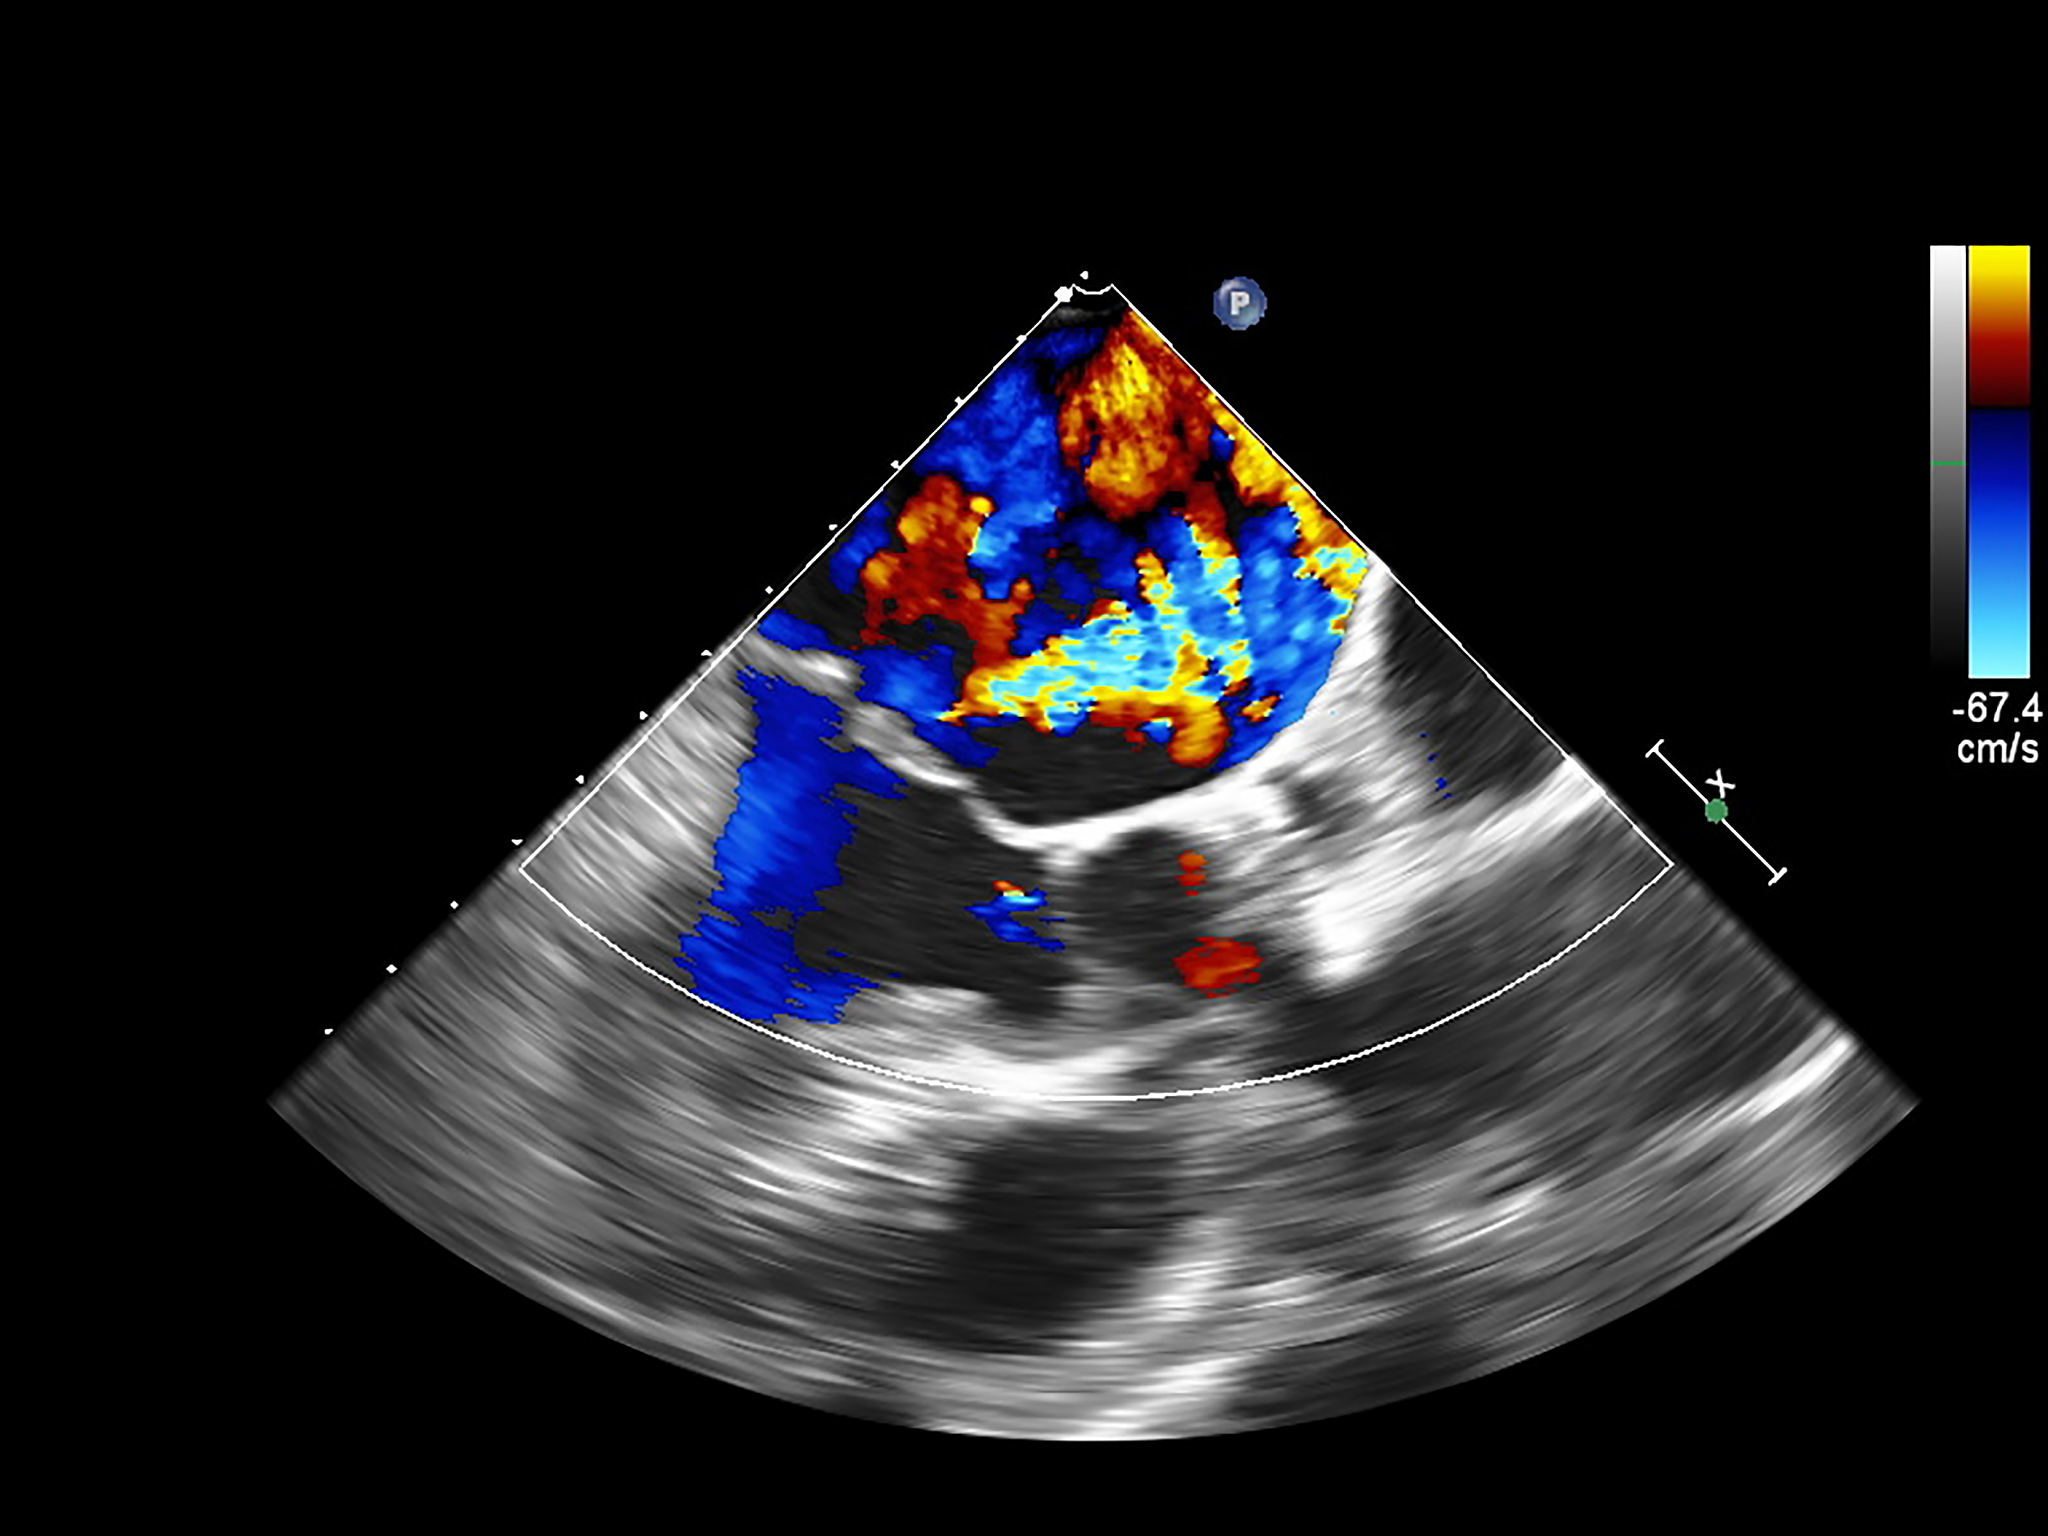

超声造影评估新生血管生成与巨噬细胞浸润的相关性

超声造影技术显示,新生血管生成的分级与巨噬细胞浸润区域的大小呈正相关。这意味着,随着新生血管生成程度的增加,巨噬细胞浸润的范围也会扩大。这一发现表明,超声造影可以作为一种潜在的非侵入性工具,用于评估炎症和组织修复过程中新生血管生成和巨噬细胞活性的关系。